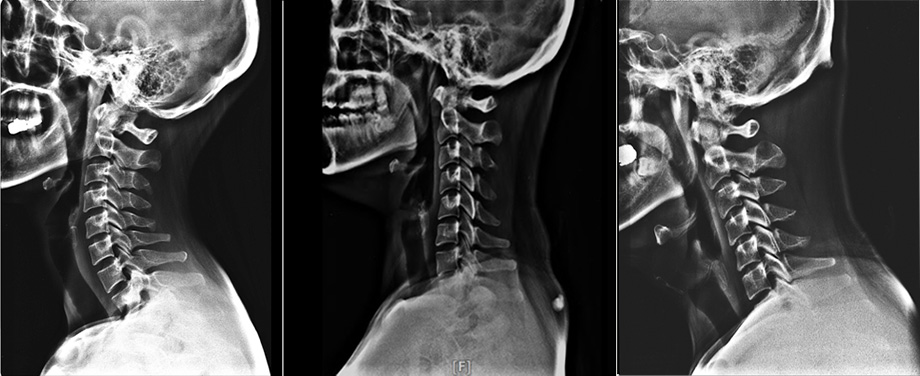

뒷목 통증을 호소하시는 분들을 보면 대부분 일자목이나 거북목인 경우가 많습니다. 목뼈는 총 7개로 C자 커브를 이루는 것이 정상적인 형태입니다. C자 커브를 형성함으로써 외부의 충격을 잘 흡수할 수 있고 머리를 잘 받쳐주니까 목이 뒤에서 받는 하중을 분산시켜주는 역할을 하게 됩니다. 그런데 잘못된 자세로 스마트폰을 보는 동작을 반복하다 보면 거북목처럼 목을 쭉 뺀 자세를 자연스럽게 취하게 되는데 이런 자세가 오랜 시간 유지되면 C자 커브는 일자목이나 거북목, 역C자로 변형이 나타납니다. 목 뼈 배열의 변형은 겉으로 보기에도 좋지 않을뿐더러 목 뒤쪽 근육이 받는 하중이 증가하면서 피로도가 증가하고 외부 충격에도 취약해집니다.

목통증이 있다면 X-ray 검사를 통해 목 상태를 확인해보는 것이 좋습니다. 거북목인 경우 어깨 중심에서 귀가 앞으로 나와있는 형태를 보고 확인이 가능하지만 일자목의 경우 겉으로 드러나지 않는 경우가 많습니다. 이때 X-ray 검사를 해보면 목 뼈의 배열이 실제로 1자가 되었는지, 거북목 형태로 되어 있는지 확인할 수 있어 보다 정확하게 진단할 수 있습니다.